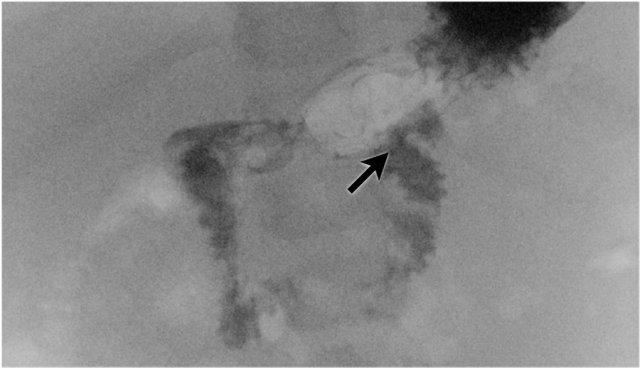

Đây là một trường hợp điển hình khác của viêm ruột hoại tử.

Lưu ý hình ảnh khí trong tĩnh mạch cửa (mũi tên) và các nhánh tĩnh mạch cửa ngoại vi.

Dấu hiệu này được thấy trên X-quang và siêu âm.